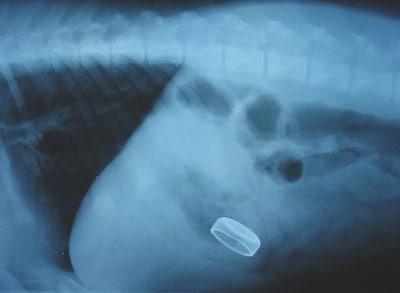

A client presents a 25-pound dog (11.4 kg) who was just observed swallowing a bottle cap.

Which one of the following choices would be the safest approach for this dog.